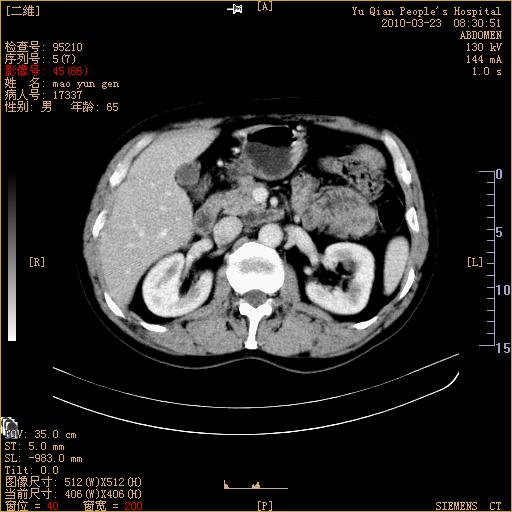

标题: CT25266:消瘦月余,前来肝部检查,请看看肠腔 [打印本页]

标题: CT25266:消瘦月余,前来肝部检查,请看看肠腔

肝区结肠占位,腺癌可考虑,建议肠镜活检。

升结肠肠壁增厚,不均强化,考虑升结肠腺癌可能性,建议肠镜检查。

1)考虑升结肠癌。2)右肾小囊肿。